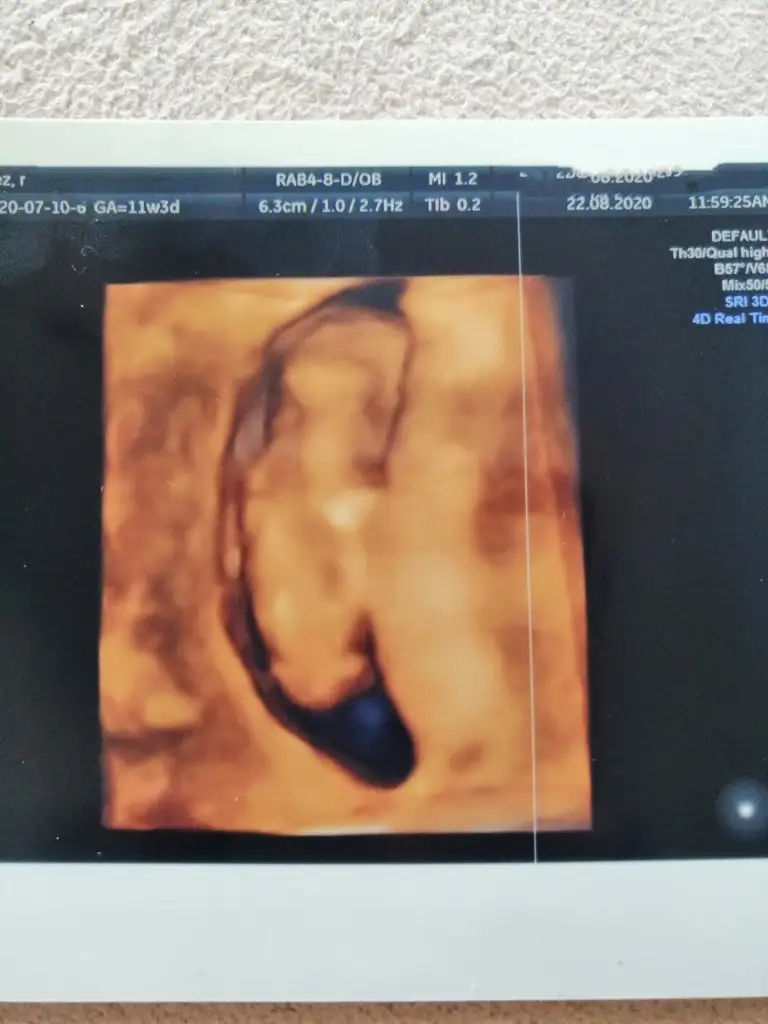

Eki Görüntüle 473828

gordugunuz gibi ust taraftaki simgedende anlasildigi gibi eger cikinti paralel ise kiz

yok 30°lik bir aciyla yukari dogru bakiyorsa %99 oglunuz olacak demektir simdi bi kac ornek resimler daha koyacagim kiziminkide dahil